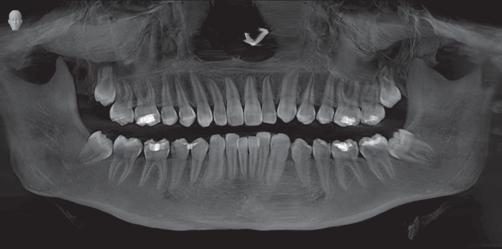

Do I really need to remove my wisdom teeth, they don’t hurt?

Through the studies of ancient tribes there was a time where one’s jaws were big enough to accommodate 32 teeth. Through environment and dietary changes we no longer have room for the third set of molars, also called wisdom teeth. When these teeth cannot erupt in to the mouth correctly they often become “impacted” or stuck in a crooked position. This impaction causes several problems which are not always painful including:

• Damage to other teeth: by crowding and pushing other teeth causing pain and bite problems

• Jaw damage: cysts can form around the third molars causing bone loss and damage to the nerve

• Sinus Issues: pain, pressure and congestion

• Inflamed gums: tissue can swell and may be hard to keep clean & lead to gum infection

• Cavities: swollen, infected gums can create pockets between teeth that help bacteria form and cavities will develop

• Alignment: the third molars can cause crowding and create the need for orthodontics to straighten teeth for a healthy smile

• Vertigo: commonly known as dizziness which is caused by the pressure of the wisdom teeth on the nerve which leads to the ear, which also controls one’s balance

The jaw bone has no feeling other than the nerve that runs through it and connects to teeth from under the roots; unless your problem affects the actual nerve you may have no pain but that does not mean there is no problem-not yet!

Misaligned wisdom tooth that caused patient to lose both teeth. Impacted Wisdom teeth.